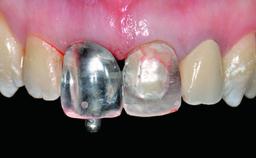

Replacement of an Ankylosed Central Incisor with a Gingival Recession: Tooth Extraction with Socket Grafting and Late Implant Placement with Simultaneous Contour Augmentation

Abutment Type CAD/CAM

Prosthesis Type FDP

Provisional Implant-Supported Prosthesis Prosthodontic margin > 3 mm apical to mucosal margin Prosthodontic margin > 3 mm apical to mucosal margin